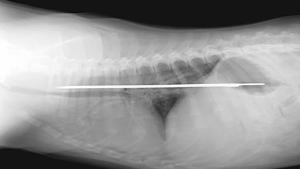

29. A Knife Inside A Puppy

Now dogs have always been known to swallow strange things. But this was an extreme case when a 13-inch serrated knife blade was found inside the puppy, stuck between the stomach and esophagus of a St. Bernard puppy in Florida. It was successfully removed thankfully.Advertisement